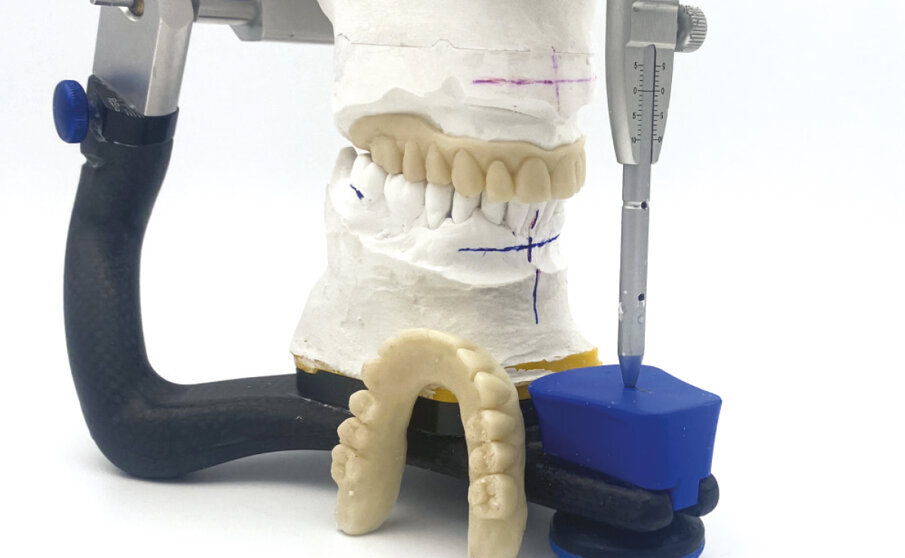

Nel laboratorio odontotecnico vengono messi in articolatore i modelli iniziali e si esegue uno studio del caso con Digital Smile Design e della situazione occlusale, per valutare eventuali rialzi della dimensione verticale e le correzioni estetiche. Le informazioni così ottenute vengono riportate nella ceratura diagnostica che in questo caso è un montaggio diagnostico/definitivo (Fig. 3). Definitivo in quanto si utilizzano già i denti del lavoro finale per il montaggio diagnostico, che vengono sfruttati per realizzare due protesi identiche in resina (Fig. 4). La prima verrà consegnata alla paziente immediatamente dopo aver inserito gli impianti. La seconda diventerà una dima protesica per la realizzazione della protesi definitiva, che verrà applicata a 7 giorni dall’intervento chirurgico.

Fig. 3 - Montaggio diagnostico.

Fig. 4 - Due protesi in resina bianca: una diventerà il provvisorio immediato per il paziente, l’altra la dima protesica.